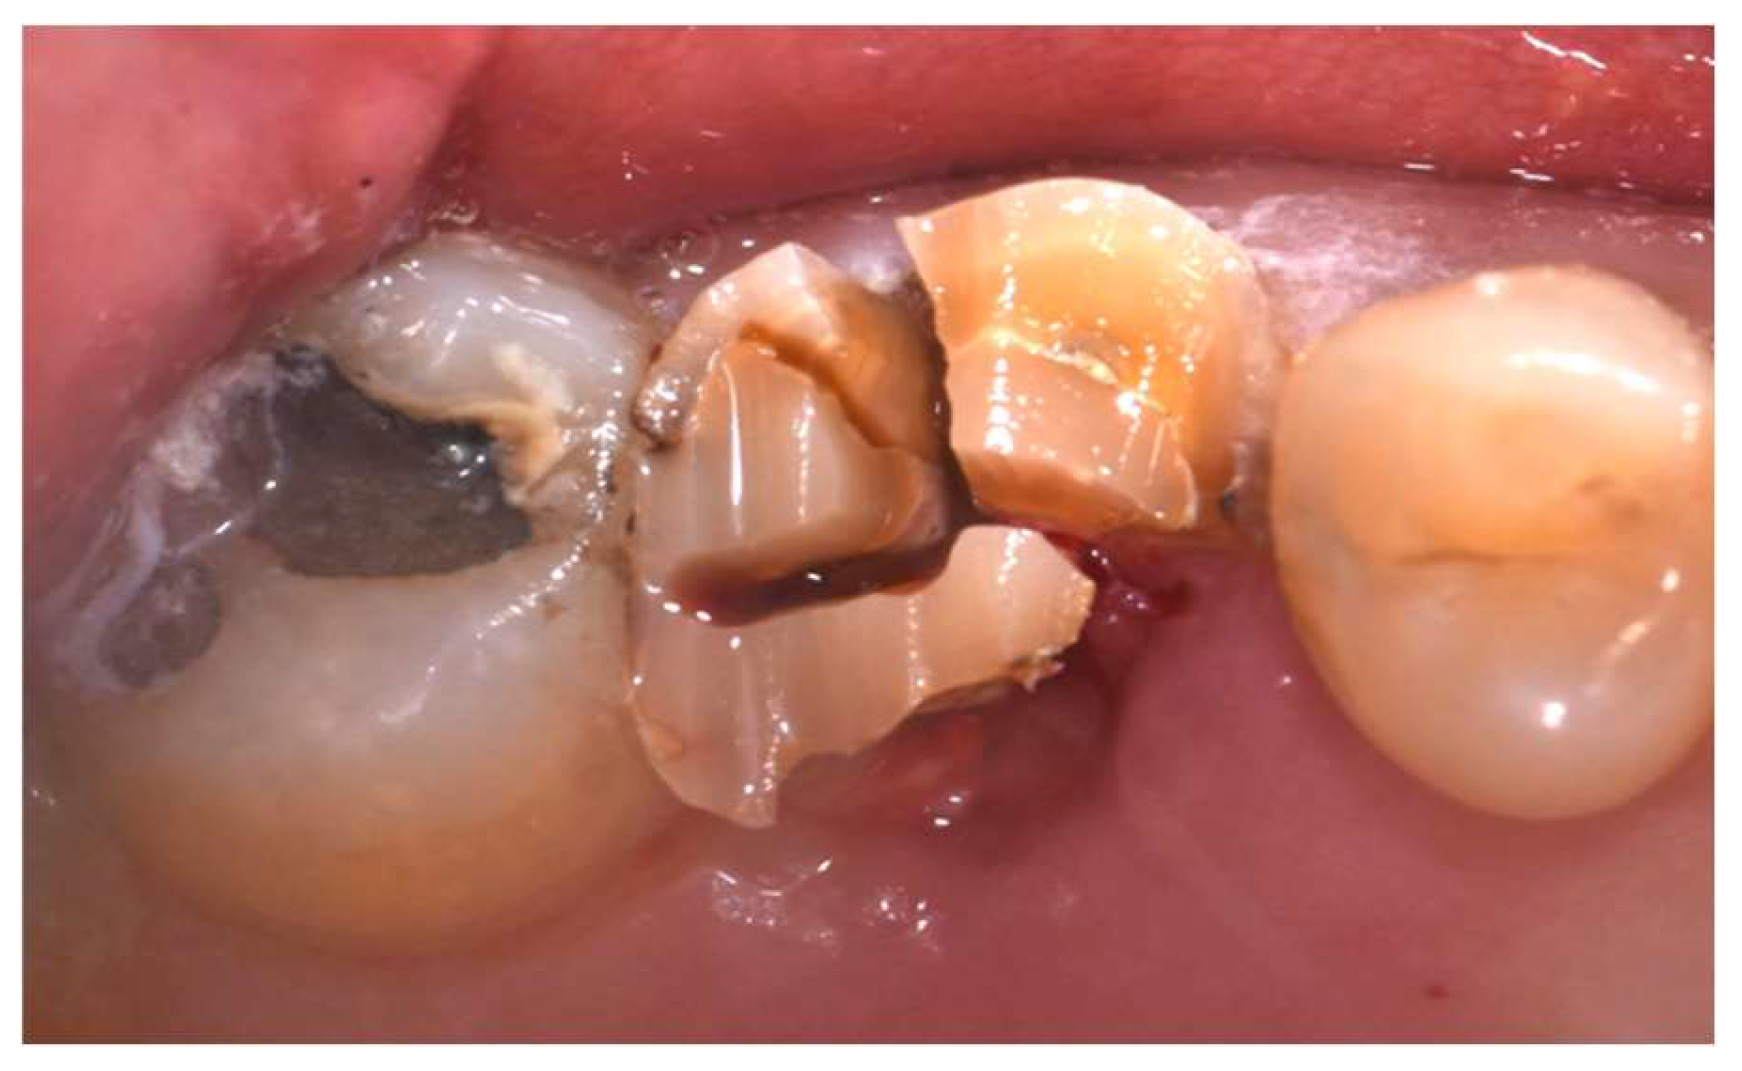

Occlusal and lateral endoral pictures of the elements to be extracted were taken before starting the surgery session (Figure 1 and Figure 2).

Figure 1, 2. Occlusal and lateral view of one of the dental element to be extracted (16).